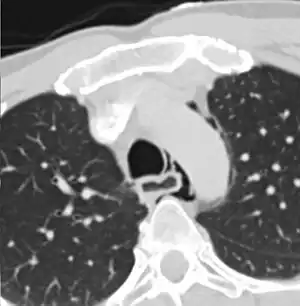

| Axial CT image through the upper chest showing extraluminal air (pneumediastinum) surrounding the trachea and esophagus | |